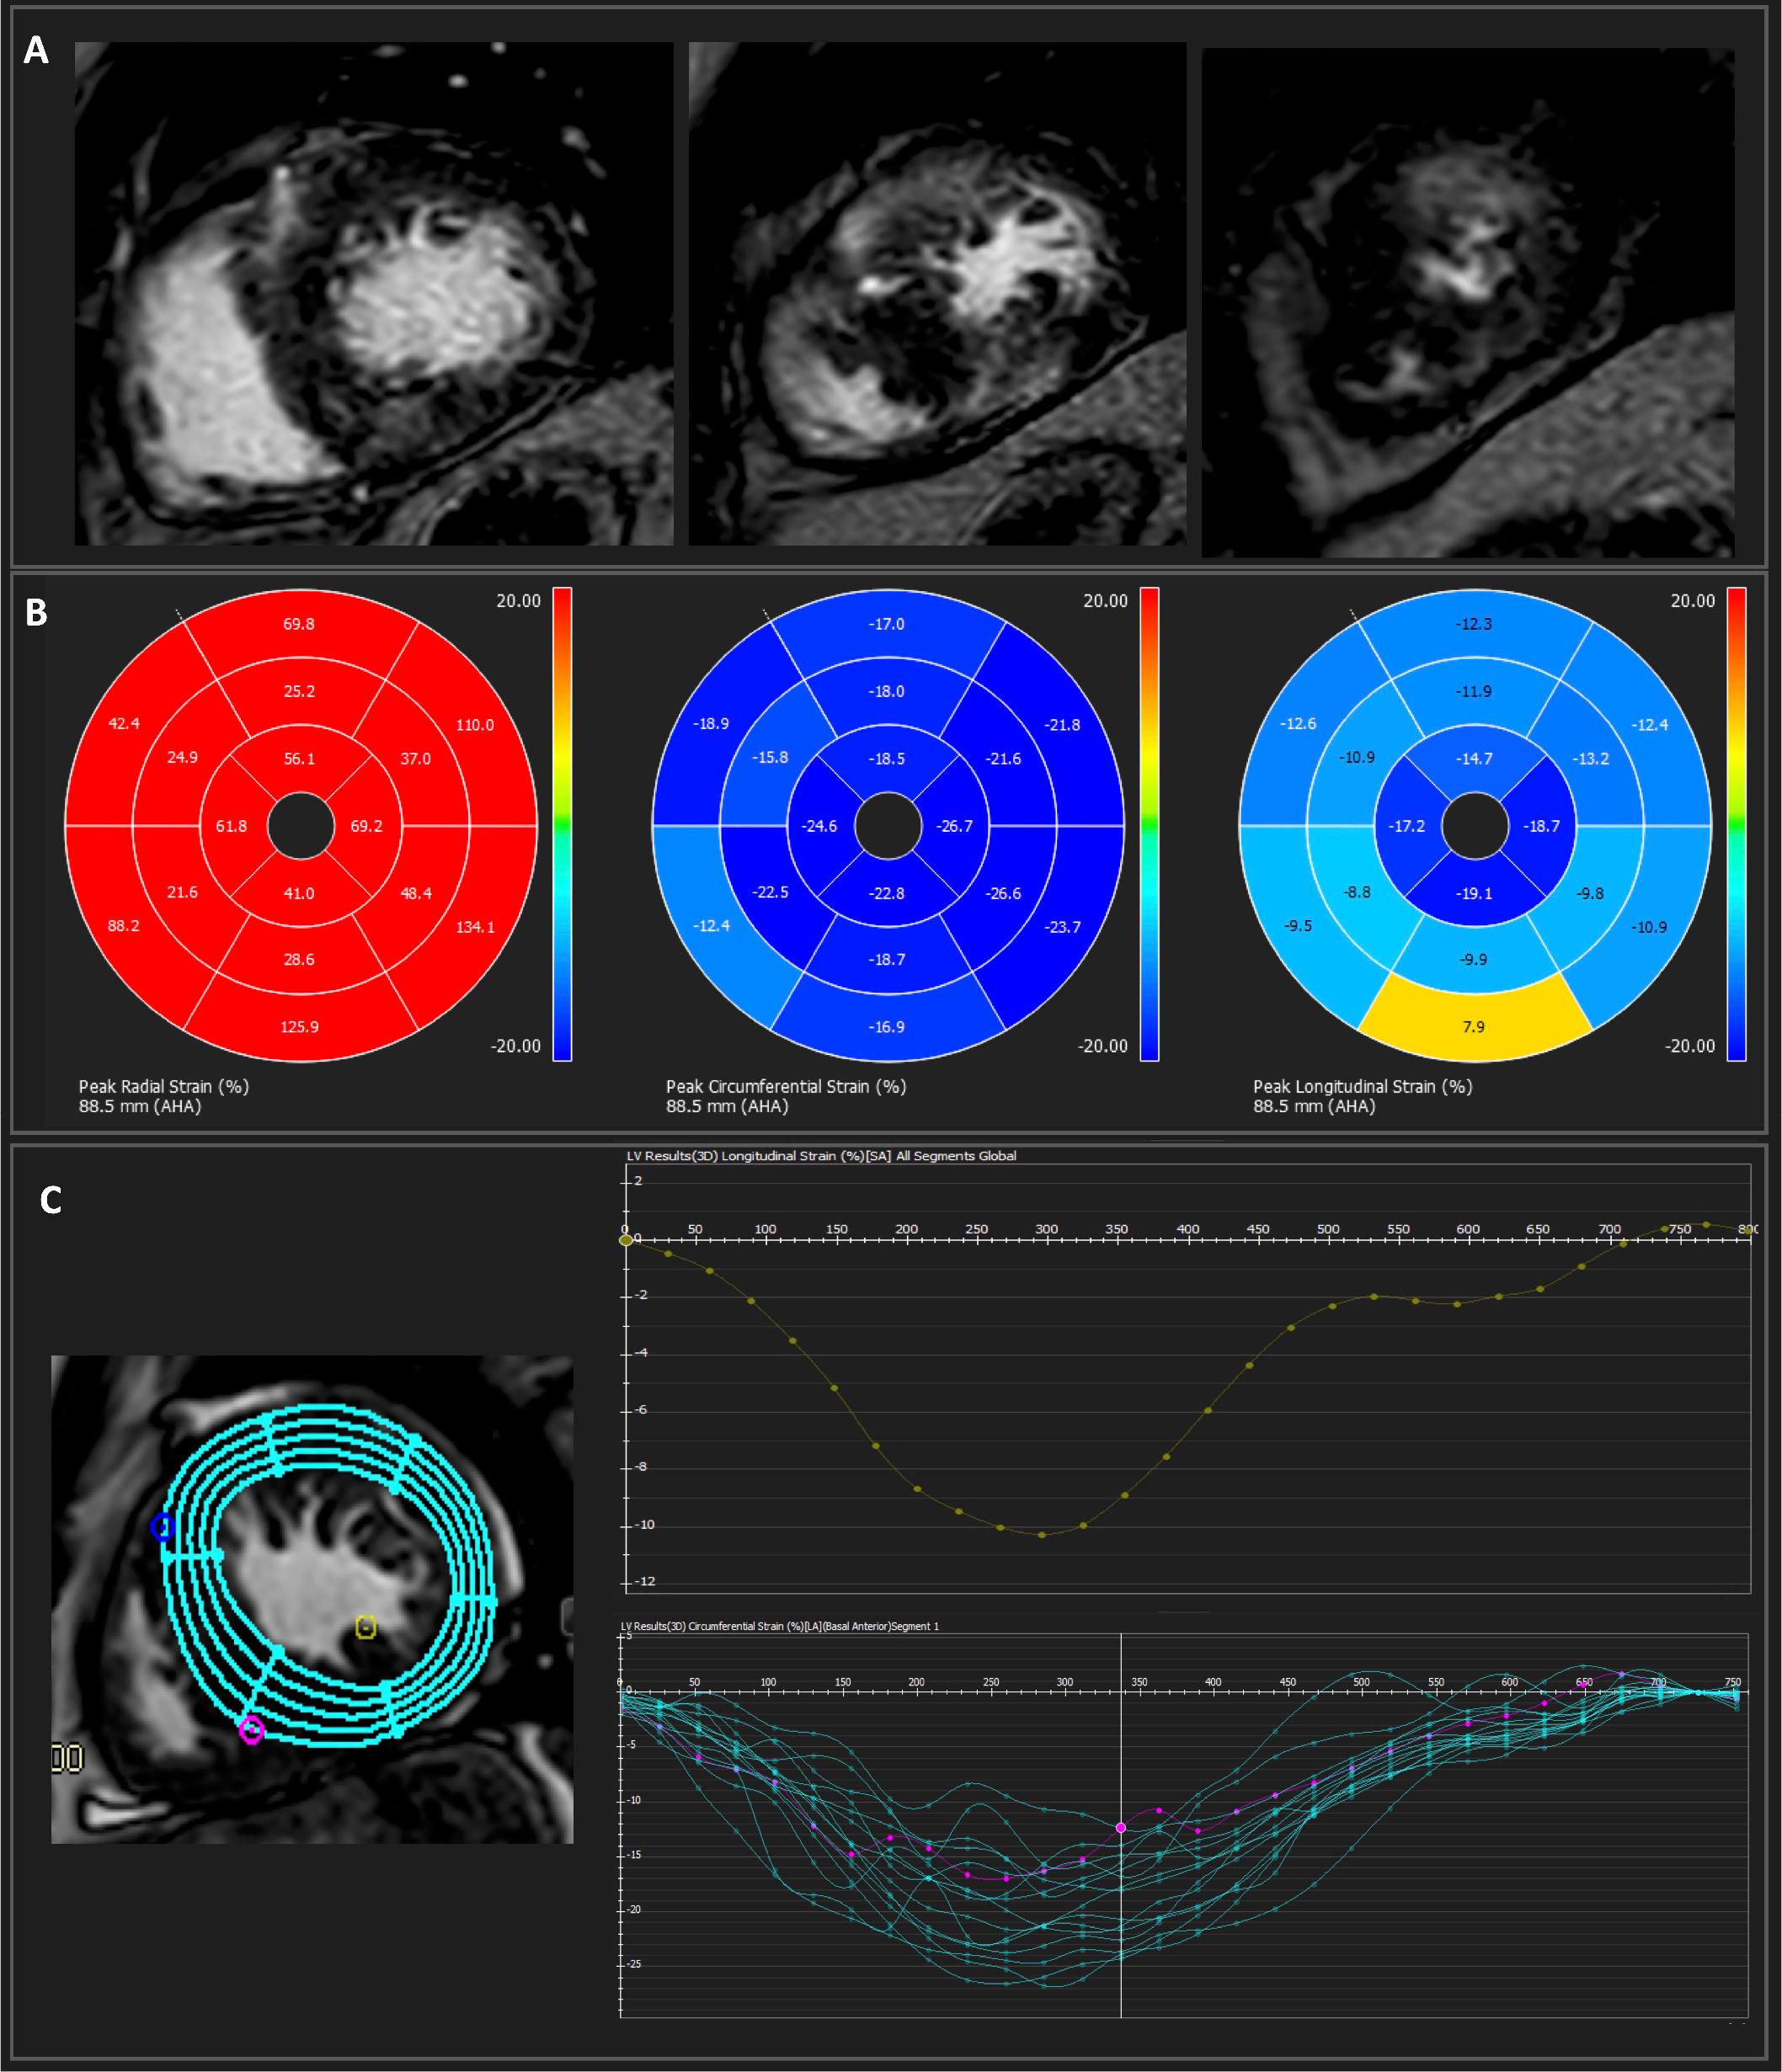

Figure 1